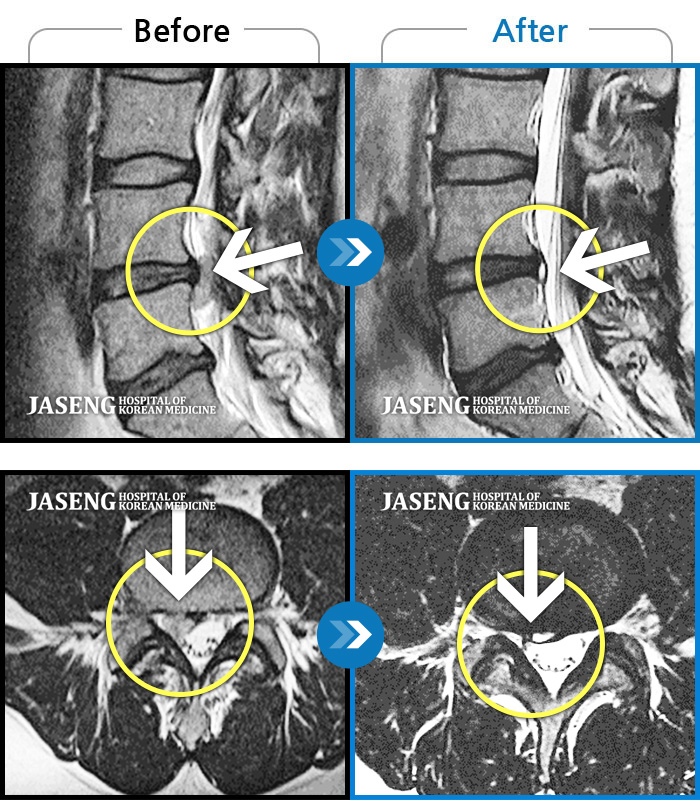

MRI 치료사례

목디스크

자고 일어난 후 발생한 극심한 후경부 통증 및 좌측 상완부의 저림

촬영시기

2024.01.11 ~ 2024.07.20

허리디스크

허리굽히는 동작을 한 후 우측 골반통증 및 우측 하지외측 저림, 근력저하가 있었다.

2023.06.15 ~ 2024.03.29

허리숙이는 일을 한 후 급격하게 발생한 우측하지 방사통, 보행장애, 야간통이 있었다.

2023.07.29 ~ 2023.12.09